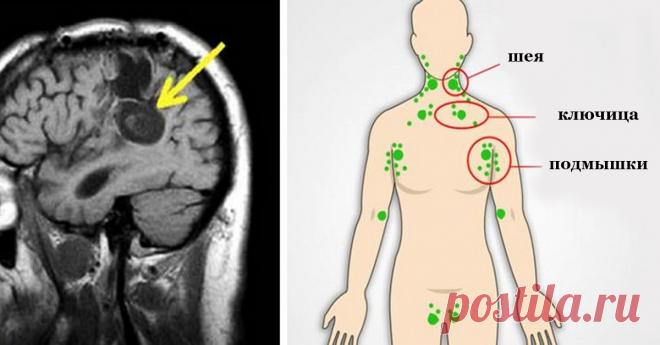

Вот, что провоцирует и ускоряет рост клеток рака в нашем теле! Узнай лучшие способы, чтобы остановить это!